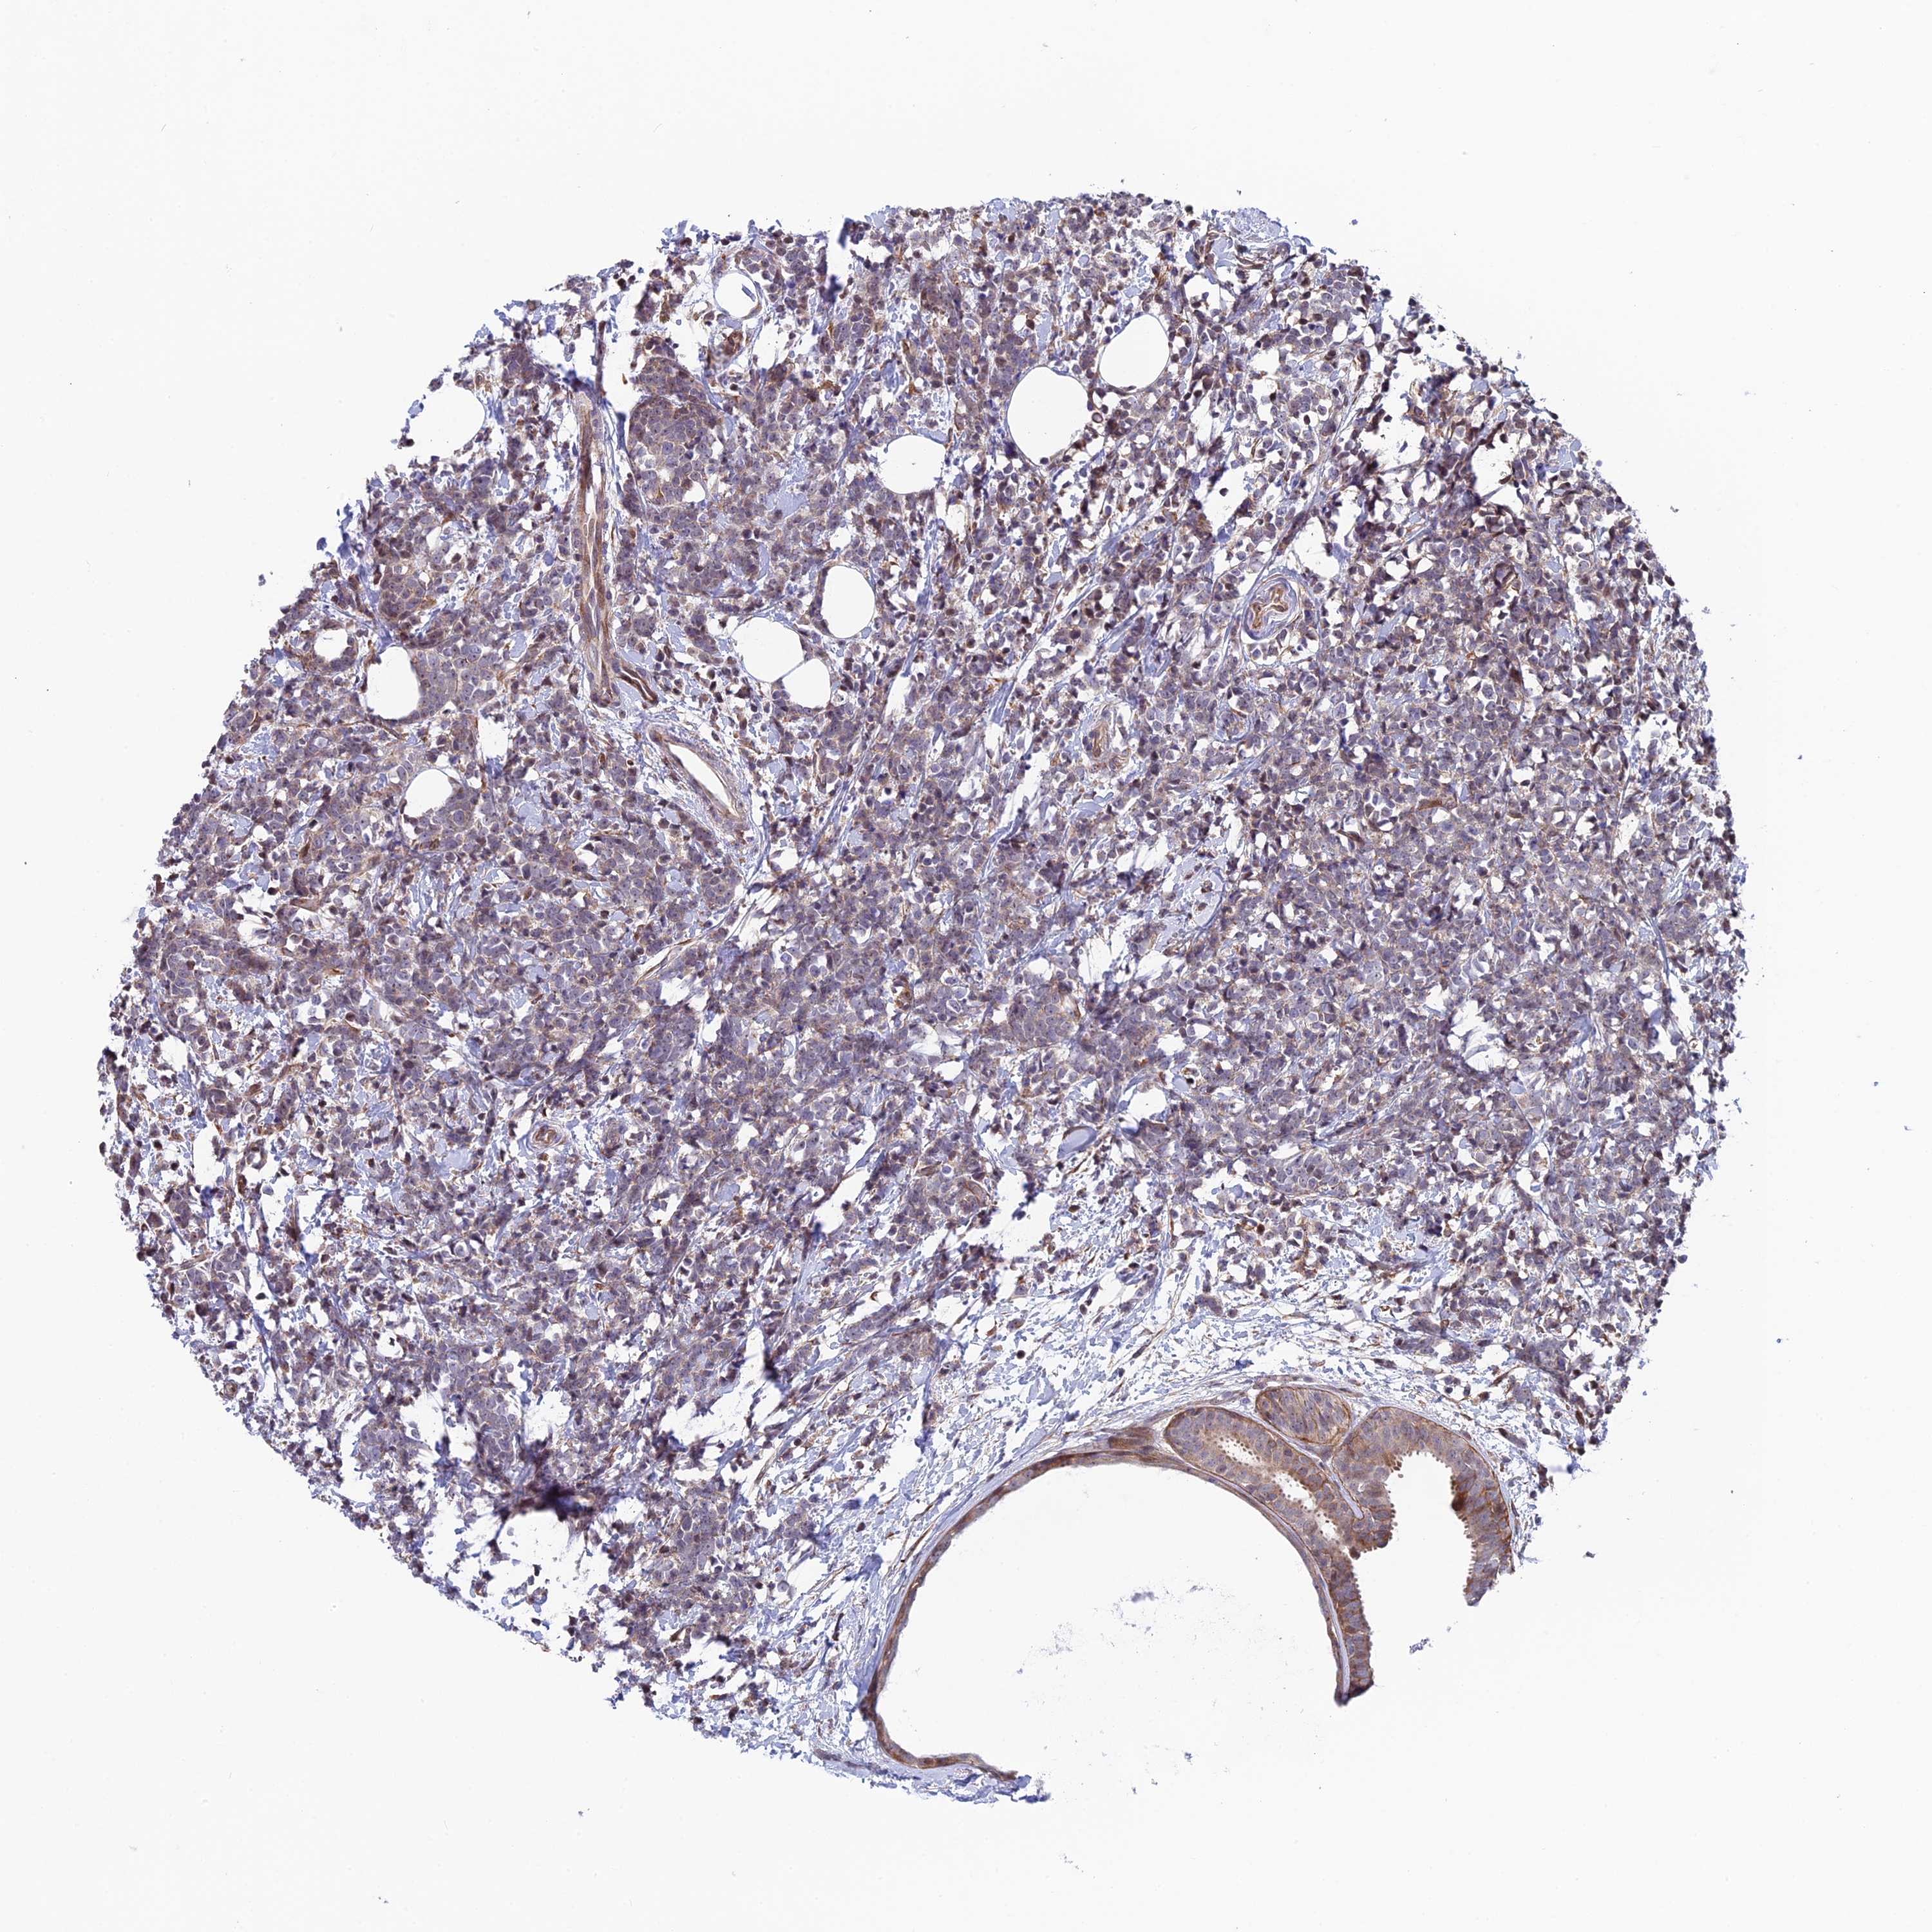

BRCA TCGA BRCA VALIDATION PROTEIN EXPRESSION

ANTIBODIES

AND

VALIDATION